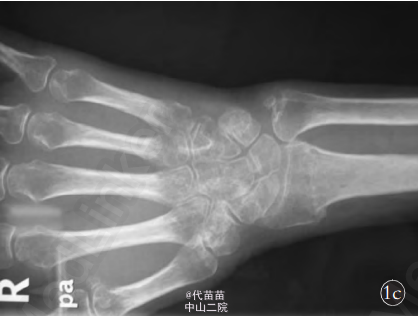

患者,女,54 岁,3 个月前不慎摔倒,右腕部着地,当即出现右腕肿胀、畸形、功能受限,于当地医院拍片后诊断为“右桡骨远端骨折、右尺骨茎突骨折”,予以骨折手法整复术,石膏托外固定。 2 个月后去除石膏托行功能锻炼,发现右手尺侧麻木不适,右手无力伴肌萎缩,小鱼际萎缩明显,抓握无力,且症状渐进性加重。在当地医院予以神经营养药物内服治疗,效果不佳,遂来本院诊治。门诊以“右尺神经损伤、右桡骨远端陈旧骨折、右尺骨茎突陈旧骨折”收入院。 入院查体:右手部肌肉萎缩,以骨间肌、小鱼际肌明显;右中环小指呈屈曲畸形,不能伸直,右手并指分指困(见图 1a,1b);右腕尺侧压 痛 明 显 ,前臂旋转功能受限。右小指掌侧及环指尺侧刺痛觉减退,夹指试验阳性。X 线片示右桡骨远端陈旧骨折、右尺骨茎突陈旧骨折(见图 1c,1d)。 肌电图(electromyography,EMG)检查见:右上肢尺神经远端支配肌见自发电活动, 见小指展肌少量新生电位。神经传导速度(never conduction velocity,NCV)检测示右上肢尺神经远端感觉运动传导未引出。 神经干动作电位(nerveaction potential,NAP)检测示神经干电位传导双侧对称。 提示:右上肢尺神经腕部不完全损伤电生理表现。诊断:右尺神经损伤;右桡骨远端陈旧骨折;右尺骨茎突陈旧骨折。 在臂丛麻醉下行右尺神经损伤探查松解术。 术中于右腕掌尺侧缘尺神经走行部位 ,取“S”形切 口 长 约 10 cm,逐 层 暴露,见尺神经在腕部走行异常,同时取腕背尺侧纵行切口长约6 cm,在显微镜下沿尺神经仔细分离,发现尺神经绕尺骨小头颈部近端尺 侧 至 尺 骨 小 头 背 侧 卡 压 于 尺 骨 茎 突 骨 折 端 部 位(见图 1e),神经明显充血、变细、变长,与周围组织粘连严重。摘除尺骨茎突碎骨快,予以尺神经彻底松解(见图 1f)。 术中见三角纤维软骨损伤,予以修补,神经外膜下注射得宝松,并用可吸收生物膜包裹,防止术后神经粘连。 术后 1 d 患者自觉疼痛缓解,环、小指麻木减轻,3 周后拆石膏托开始功能锻炼。5 个月后随访,患者自觉症状全部消失 ,环、小指感觉恢复正常,手指伸直、屈曲功能及分指、并指功能良好(见 图 1g,1h,1i),小鱼际肌及骨间肌萎缩明显恢复,前臂旋转功能良好。 本例患者受伤时,腕关节处于背伸位,前臂旋前,手掌着地,强大的暴力作用于手掌,桡骨远端骨折向背侧移位,腕缺乏支撑,造成腕尺侧继续损伤,尺骨茎突骨折及腕部三角纤维软骨损伤, 同时桡骨骨折近端及尺骨茎突骨折近端向掌侧重叠移位, 使尺骨茎突骨折端嵌插于尺神经的掌尺侧,导致尺神经绞索于尺骨小头桡背侧及尺骨茎突骨折近端,此时经手法牵引复位后,造成尺神经被卡压于骨折断端。其损伤机制不同于通常的桡骨远端骨折引起腕尺管周围软组织的粘连、瘢痕使尺神经及其分支造成压迫而产生的尺神经损伤。因患者术后腕部肿胀、疼痛,再加上石膏托固定,患肢不能活动,很难在早期发现,极易漏诊而得不到及时处理。 因此手法复位前后需注意患指的感觉、运动情况,判断手法复位前后有无正中神经损伤或尺神经损伤。若发现损伤,必须立即做相应处理。 治疗方法:尺神经是支配手内在肌的主要神经,损伤后会对手部功能产生重要影响,损伤后修复越早,效果越好。 当腕部尺神经损伤诊断一旦明确,手内在肌萎缩,肌电图有失神经电位者,必须尽早行神经探查松解术,以便解除神经的压迫,改善神经局部的血流障碍,降低神经内液压,维持神经内环境的稳定性,促进纤维再髓鞘,恢复其正常的传导功能。 术中在显微镜下细心的彻底松解卡压的神经,避免二次损伤。术中神经虽然明显水肿、充血、变细 、变长,但仍有部分神经纤维连续,术前肌电图显示尺神经腕部不完全损伤电生理表现,故仅仅给予神经松解,未予切断重新吻合。 如卡压非常严重,无明显神经束相连,切除神经瘤,行神经的直接吻合或桥接神经移植。神经受伤的程度、位置、手术的时间、是否采用显微外科技术修复等与预后有密切的关系。 在上肢神经修复或神经松解术后尺神经效果最差,重要原因为尺神经主要支配手内肌,即使神经吻合质量好, 再生过程顺利, 待其生长到运动终板时,手内肌群及运动终板已萎缩失用,疗效不佳。此例虽卡压于骨折端的骨痂内3月余,但由于尺神经未完全损伤且术中在显微镜下精细的操作,未造成二次损伤,且损伤部位在腕部近手内肌处,手术后效果仍令人满意。